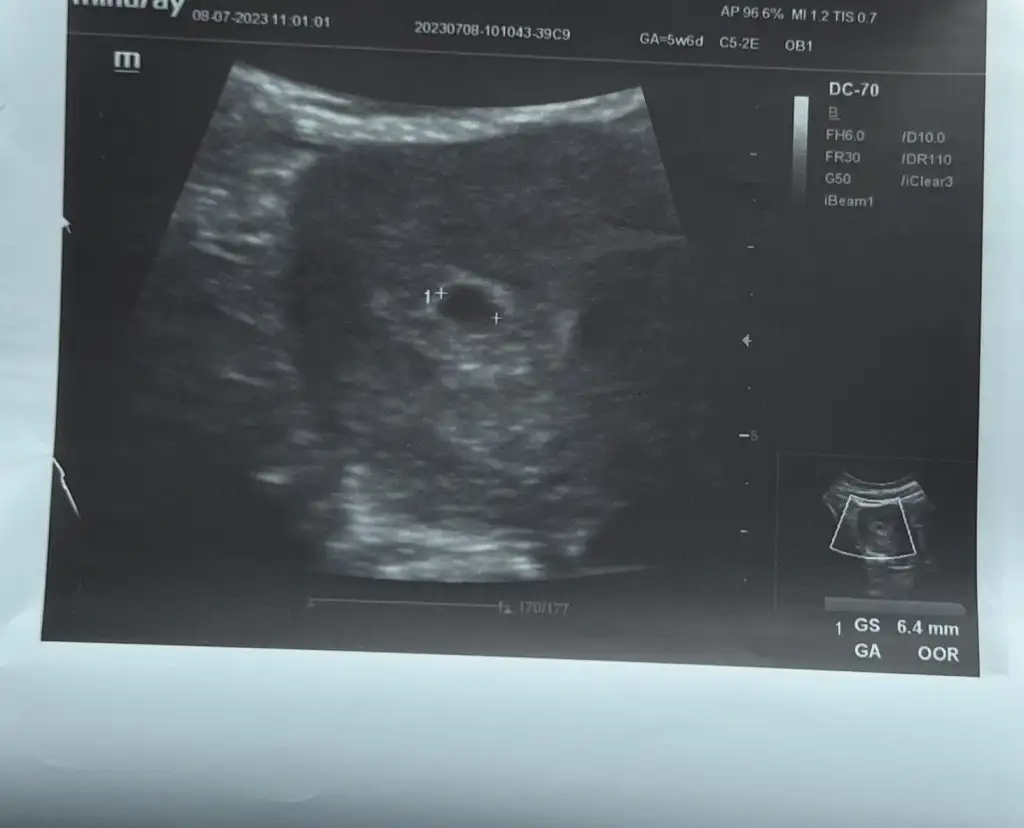

Kızlar selam tekrar, 2 gün önce doktor kontrolüm vardı keseyi gördük kalbi duyduk çok şükür28 mayıs sat, 5 mart tahmini doğum dedi doktorum haftaya tekrar gideceğim kontrole kısmetse daha net bişeyler söyler zannediyorum

kızlar merhaba bugun ilk kez keseyi gördüm ben keseyi görünce doktor tekrar beta istemedi 4+6 yız bugun salı betam 1046ydı kese görünmüyordu bugune yazmıstı bugun gördük çok şükür Alalhım hepimize sağ salim gösterein inşallah

Eklentiler

• 4E7367EB-C65C-4171-A35B-6C3DDE0AF405.webp

17,2 KB · Görüntüleme: 79